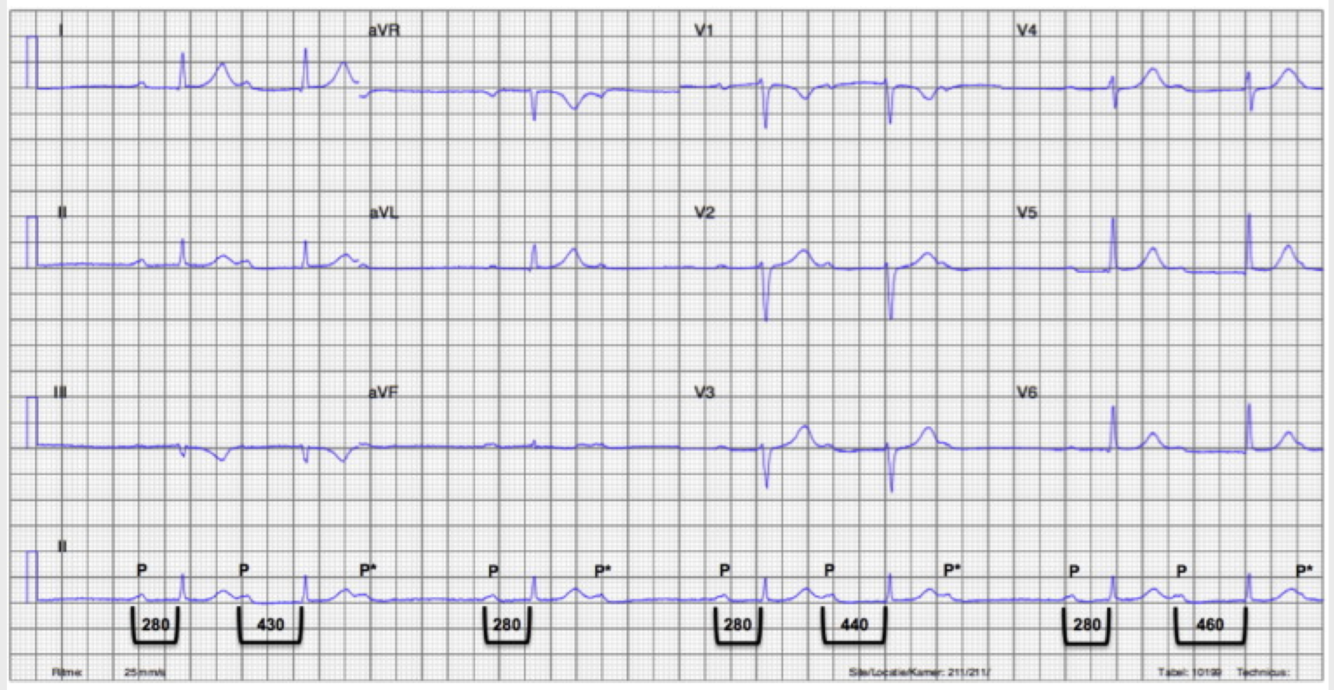

2nd-degree type 1

What kind of heart block is this?